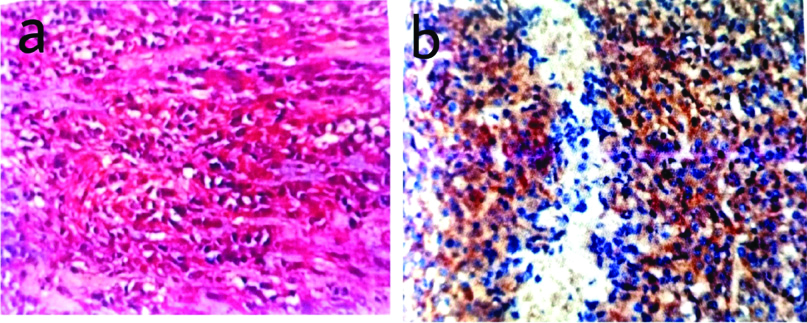

The accuracy and sensitivity of CD117 and DOG-1 in the present study which correlated with the observations of Krishnappa P et al., and Sun XW et al., respectively [21,22]. Present study results of DOG-1 positivity in CD117 negative GIST are almost similar to the findings of Lee C et al., [Table/Fig-6,7] [23].

a) Microphotograph of epithelioid GIST with prominent cytoplasmic clearing and signet ring shaped cells (H&E, X 400); b) CD117 positivity in epithelioid GIST (CD117, X 400).